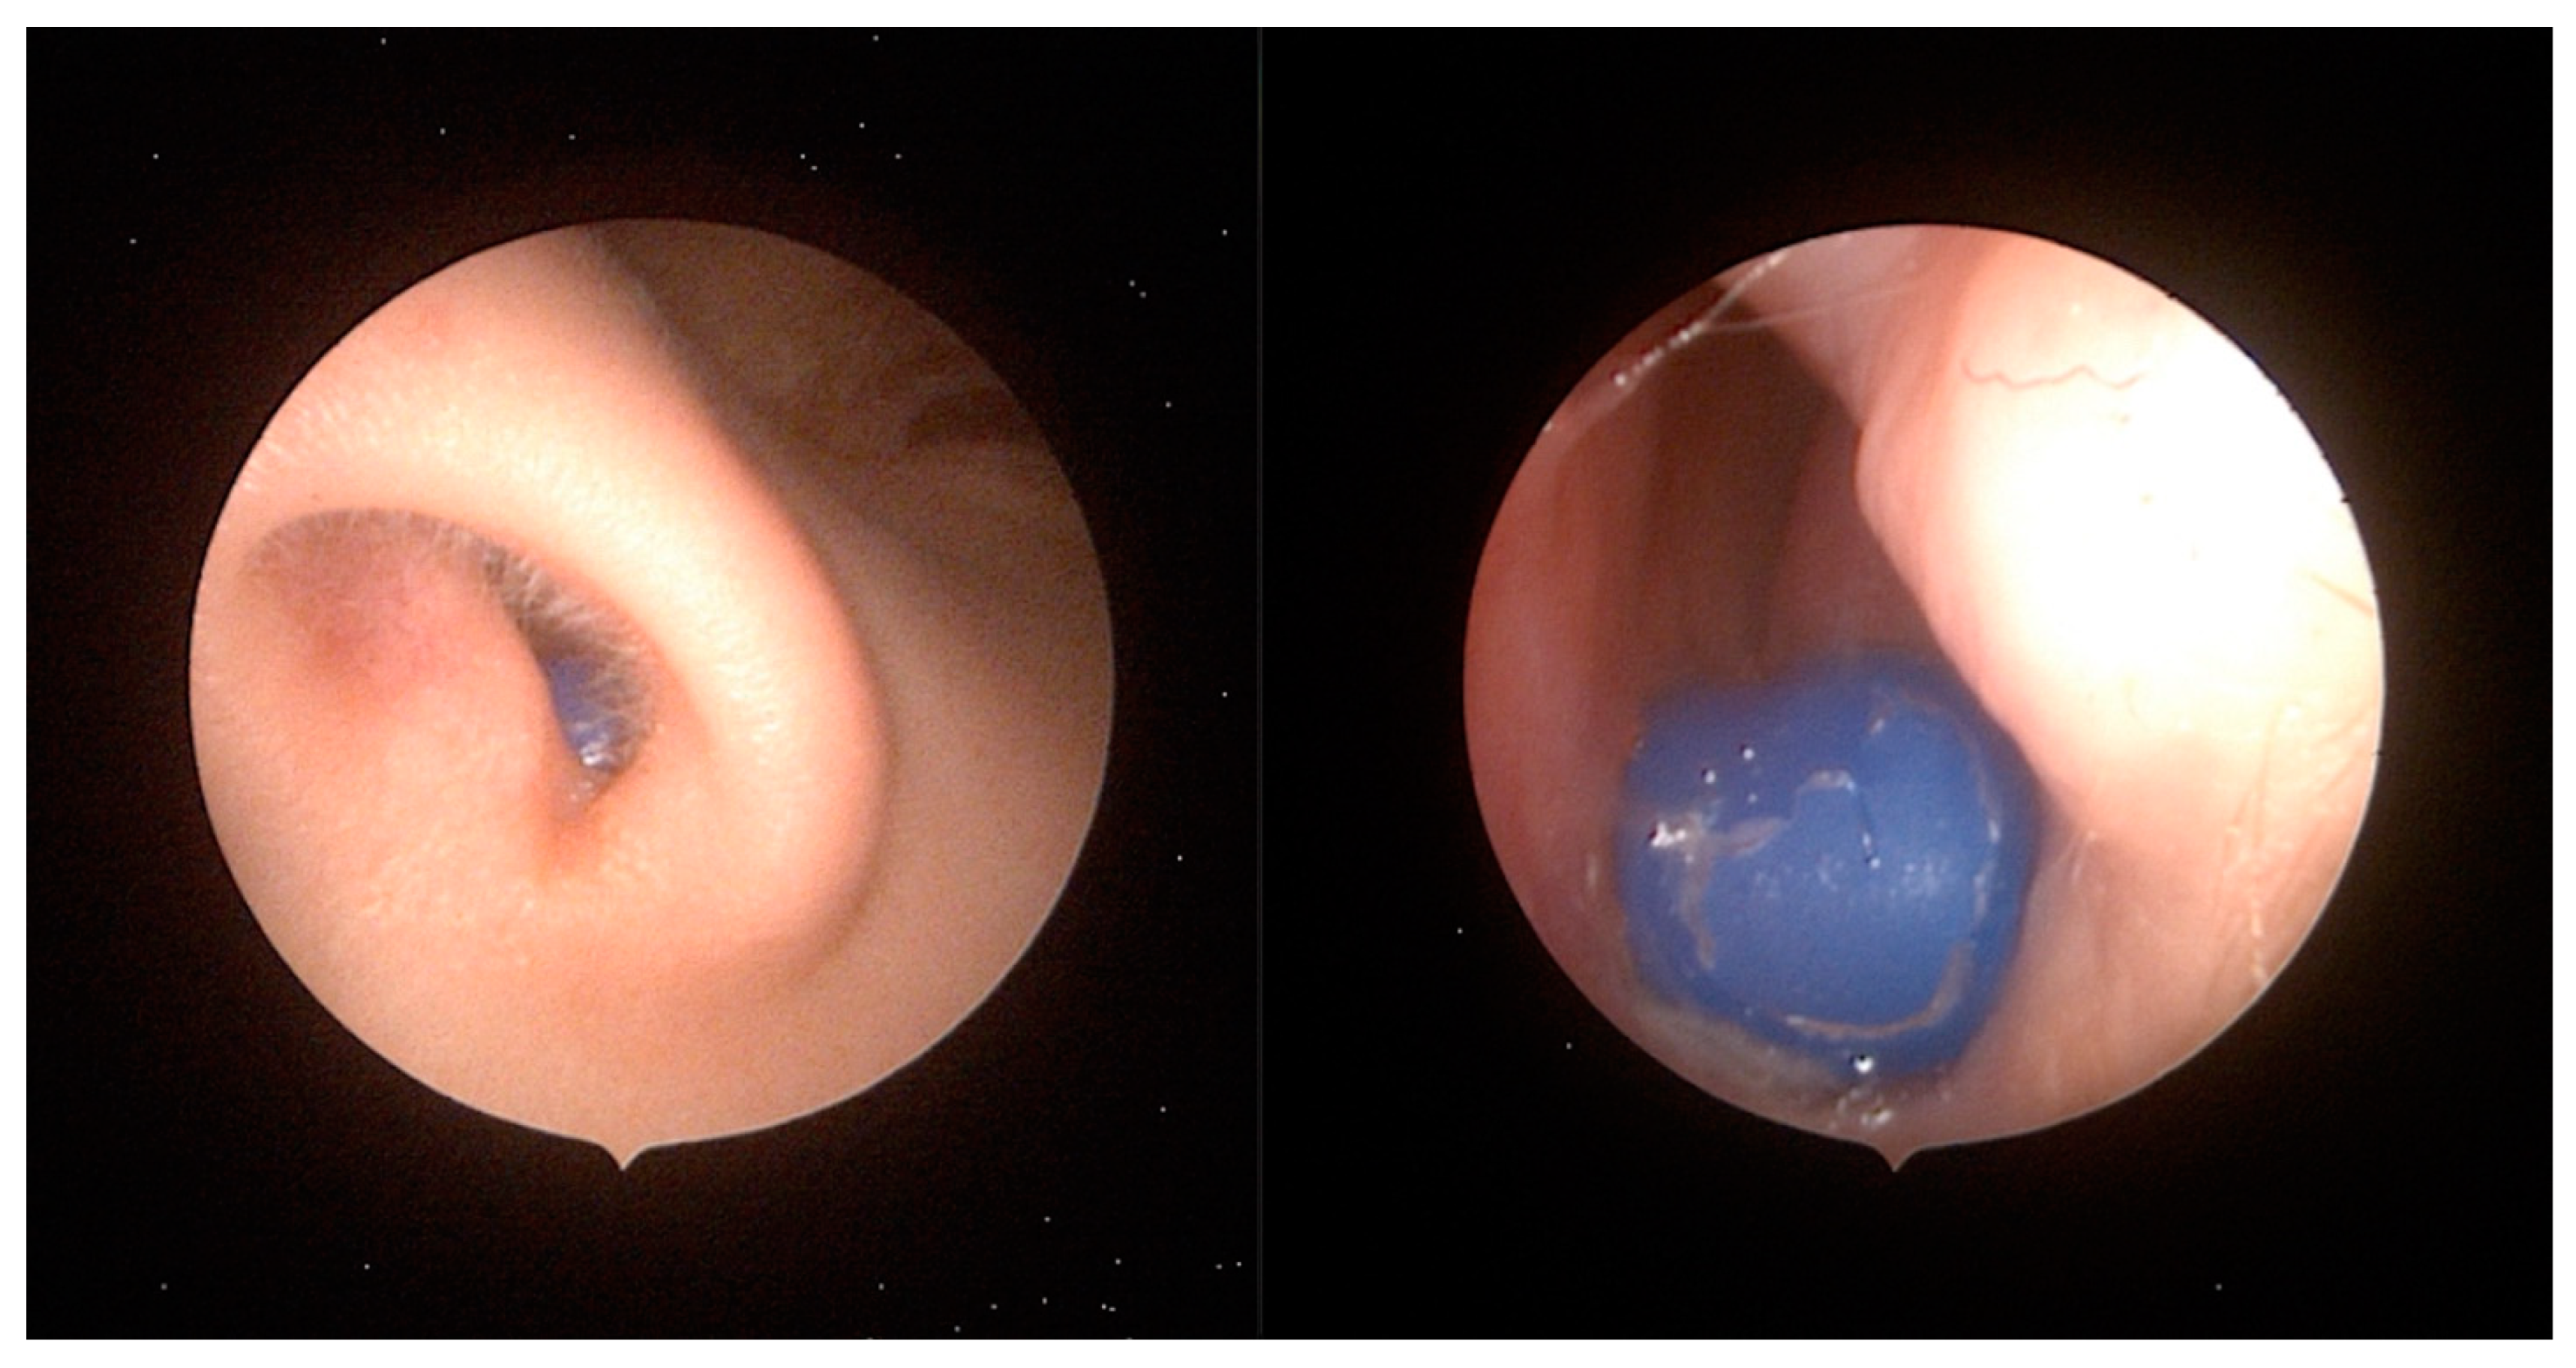

3. Nasal Foreign Bodies